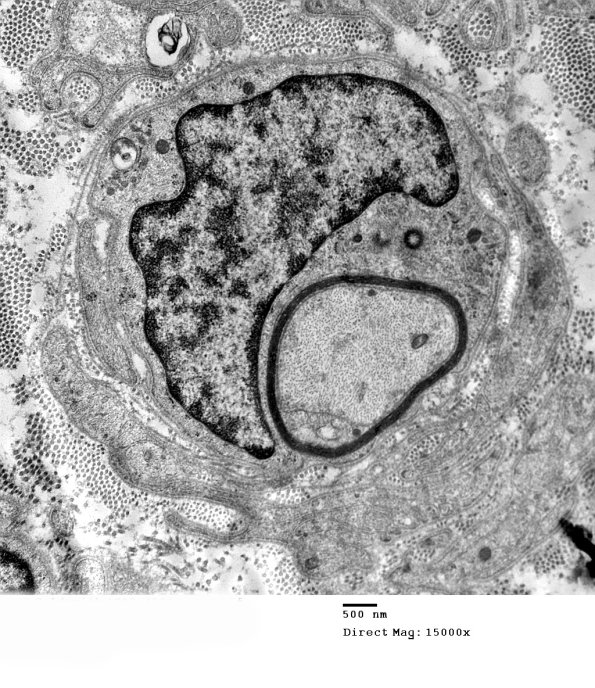

1F1A,B There is a new thin layer of myelin representing remyelination. (electron micrographs)